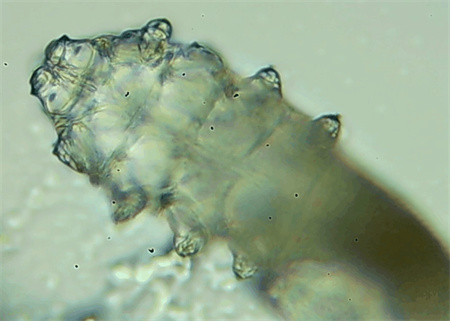

從一只眼睛的上眼瞼和下眼瞼處各拔3根睫毛,放在玻片上。

把玻片放到顯微鏡下觀察,通過電腦實時傳送的畫面,可以查看到這些拔下來的睫毛上是否有螨蟲。

結(jié)果,有6個人拔下來的睫毛上都發(fā)現(xiàn)了螨蟲。

這種螨蟲叫做蠕形螨,他們通常呈乳白色、半透明的細長狀,擁有四對腳。它們跟被子上的塵螨可不是同一種。

這些蠕形螨主要寄生在面部、頭皮、眼睛的睫毛毛囊、睫毛皮脂腺,以及瞼板腺里,以睫毛囊上皮細胞、腺體內(nèi)脂質(zhì)為食物。因此,即使經(jīng)常換洗床單、衣物,也可能會有蠕形螨。